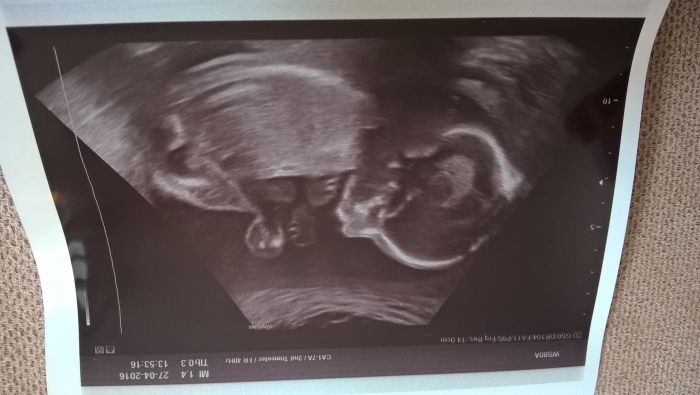

Ahoj holky, kdepak jste všechny? Já se hlásím z druhého velkého screeningu. Podle něj je vše v pořádku. Plodové vody je přiměřeně, placentu mám vlevo. Je to opravdu holčička, odpovídá 21+1 a dneska měla 403g. Viděli jsme jak si strká nožičku do pusinky... :-)

Nevím proč, ale zase se mi ty obrázky otočily... :-(